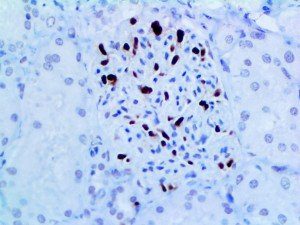

It is the ICU physician who is most likely to witness one of the deadliest manifestations of the abnormal immunological response, the cytokine storm syndrome (CSS). This response is also referred to by some as the cytokine release syndrome (CRS). CSS is characterized by continuous activation and expansion of macrophage and lymphocyte populations, which secrete large amounts of cytokines, causing the cytokine storm. This massive cytokine release is akin to hemophagocytic lymphohistiocytosis (HLH) disease, a syndrome characterized by initial unchecked and persistent activation of cytotoxic T lymphocytes and NK cells.

Clinical and laboratory manifestations of HLH include fever, enlarged liver and/or spleen, neurologic dysfunction, coagulopathy, liver dysfunction, cytopenias (i.e., low levels of erythrocytes, leukocytes, and/or platelets), hypertriglyceridemia, hyperferritinemia, hemophagocytosis, and eventually diminished NK cell activity as the immune system becomes progressively paralyzed. HLH can be familial (primary HLH) or secondary to another disease process (sHLH), such as rheumatic disease, in which it is referred to as macrophage activation syndrome (MAS, characterized by elevated ferritin).